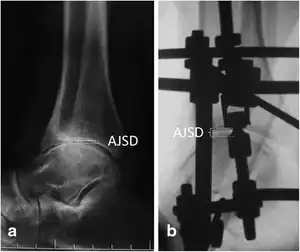

| Distraction arthroplasty- Lateral view of the ankle joint. The ankle joint space distance (AJSD) was distracted from 1.7 mm (a) preoperatively to 5.2 mm (b) postoperatively | |

- Distraction arthroplasty[3]